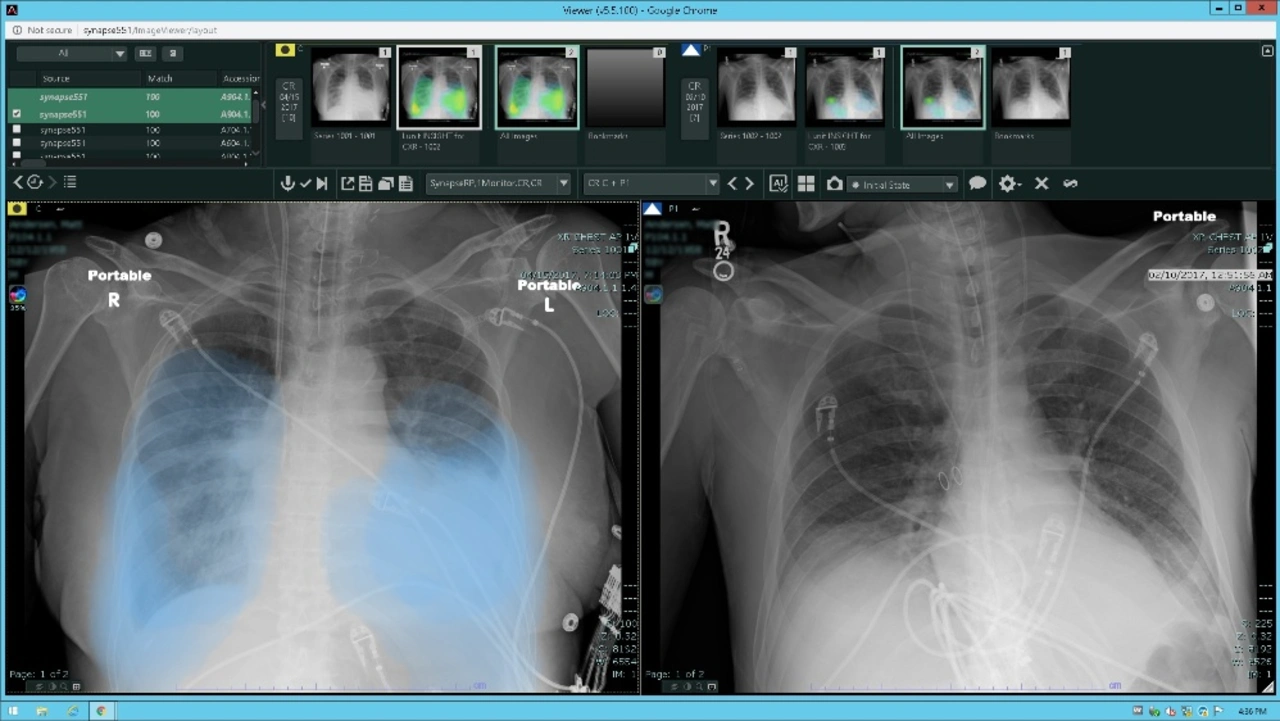

Die Verarbeitung von CT-Scans und Thorax-Röntgenaufnahmen durch REiLI stellt eine wichtige Unterstützung für den Radiologen dar und bietet ihm laut eigener Aussage eine extrem schnelle, quantitative und objektive Beurteilung der verschiedenen Zonen der Lunge. Insbesondere das Thoraxröntgen ist ein gutes Beispiel für die Anwendung der neuen KI-Technologie, da es sich um eine schnelle und einfache Untersuchung handelt, die eine Vielzahl nützlicher Informationen zur Bewertung der, durch das Virus verursachten, Lungenparenchym Konsolidierung liefert.

REiLI identifiziert verschiedene Befunde interstitieller Lungenentzündung, die auf CT-Bildern erscheinen, und berechnet deren Verteilung und Volumen.

Das Modul Lunit Insight CXR zur Analyse und Detektion der wichtigsten Lungenerkrankungen (Knötchen, Atelektase, Fibrose, Verkalkungen, Kardiomegalie usw.) ist in die REiLI-Plattform integriert. Aus gegebenem Anlass wurde das Modul aktualisiert, um bei der Identifizierung der durch das Virus verursachten Lungenparenchym Konsolidierung zu unterstützen.